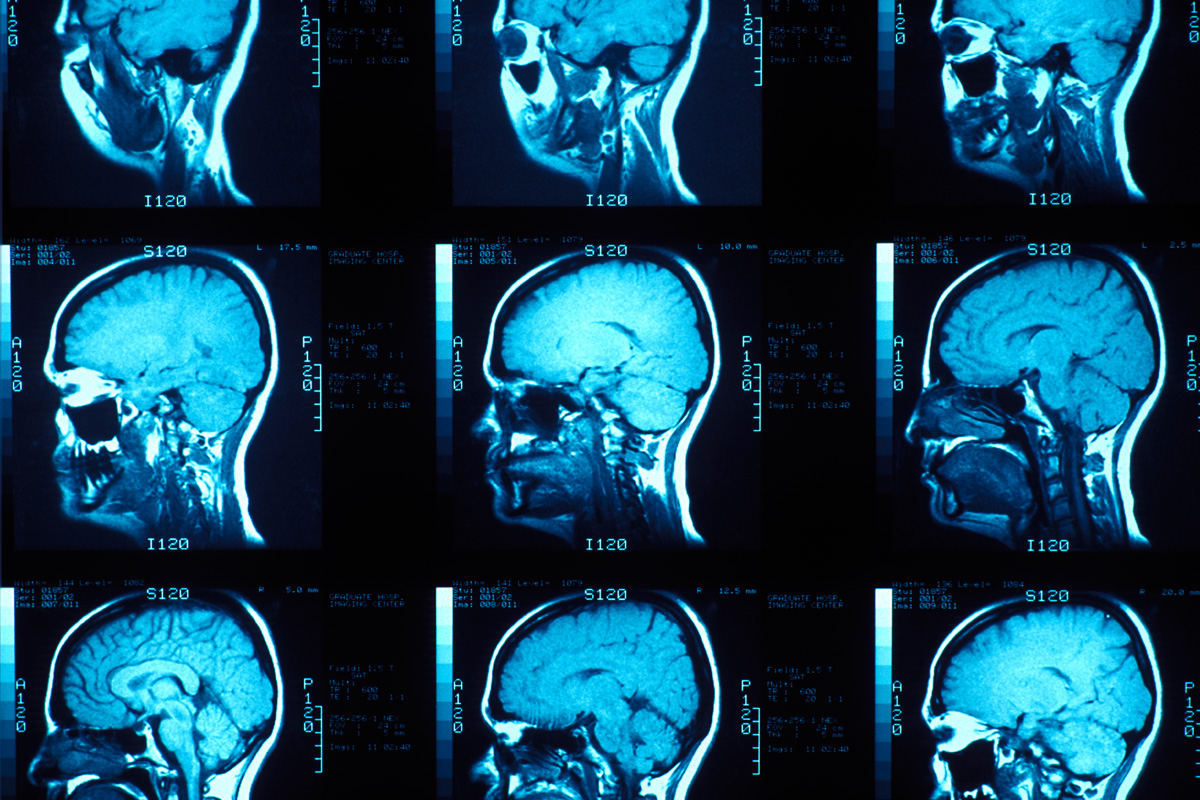

El estudio analizó imágenes de resonancia magnética de 120 adultos en Estados Unidos para observar cómo ciertas regiones del cerebro se relacionan con rasgos típicos de la psicopatía, como la impulsividad, la búsqueda constante de estímulos y la falta de empatía.

Los resultados mostraron que las personas con tendencias psicopáticas tienen un estriado un 10 % más grande que el promedio. Esta estructura cerebral está vinculada con la toma de decisiones, la motivación y la búsqueda de recompensas, funciones directamente asociadas a la conducta impulsiva.